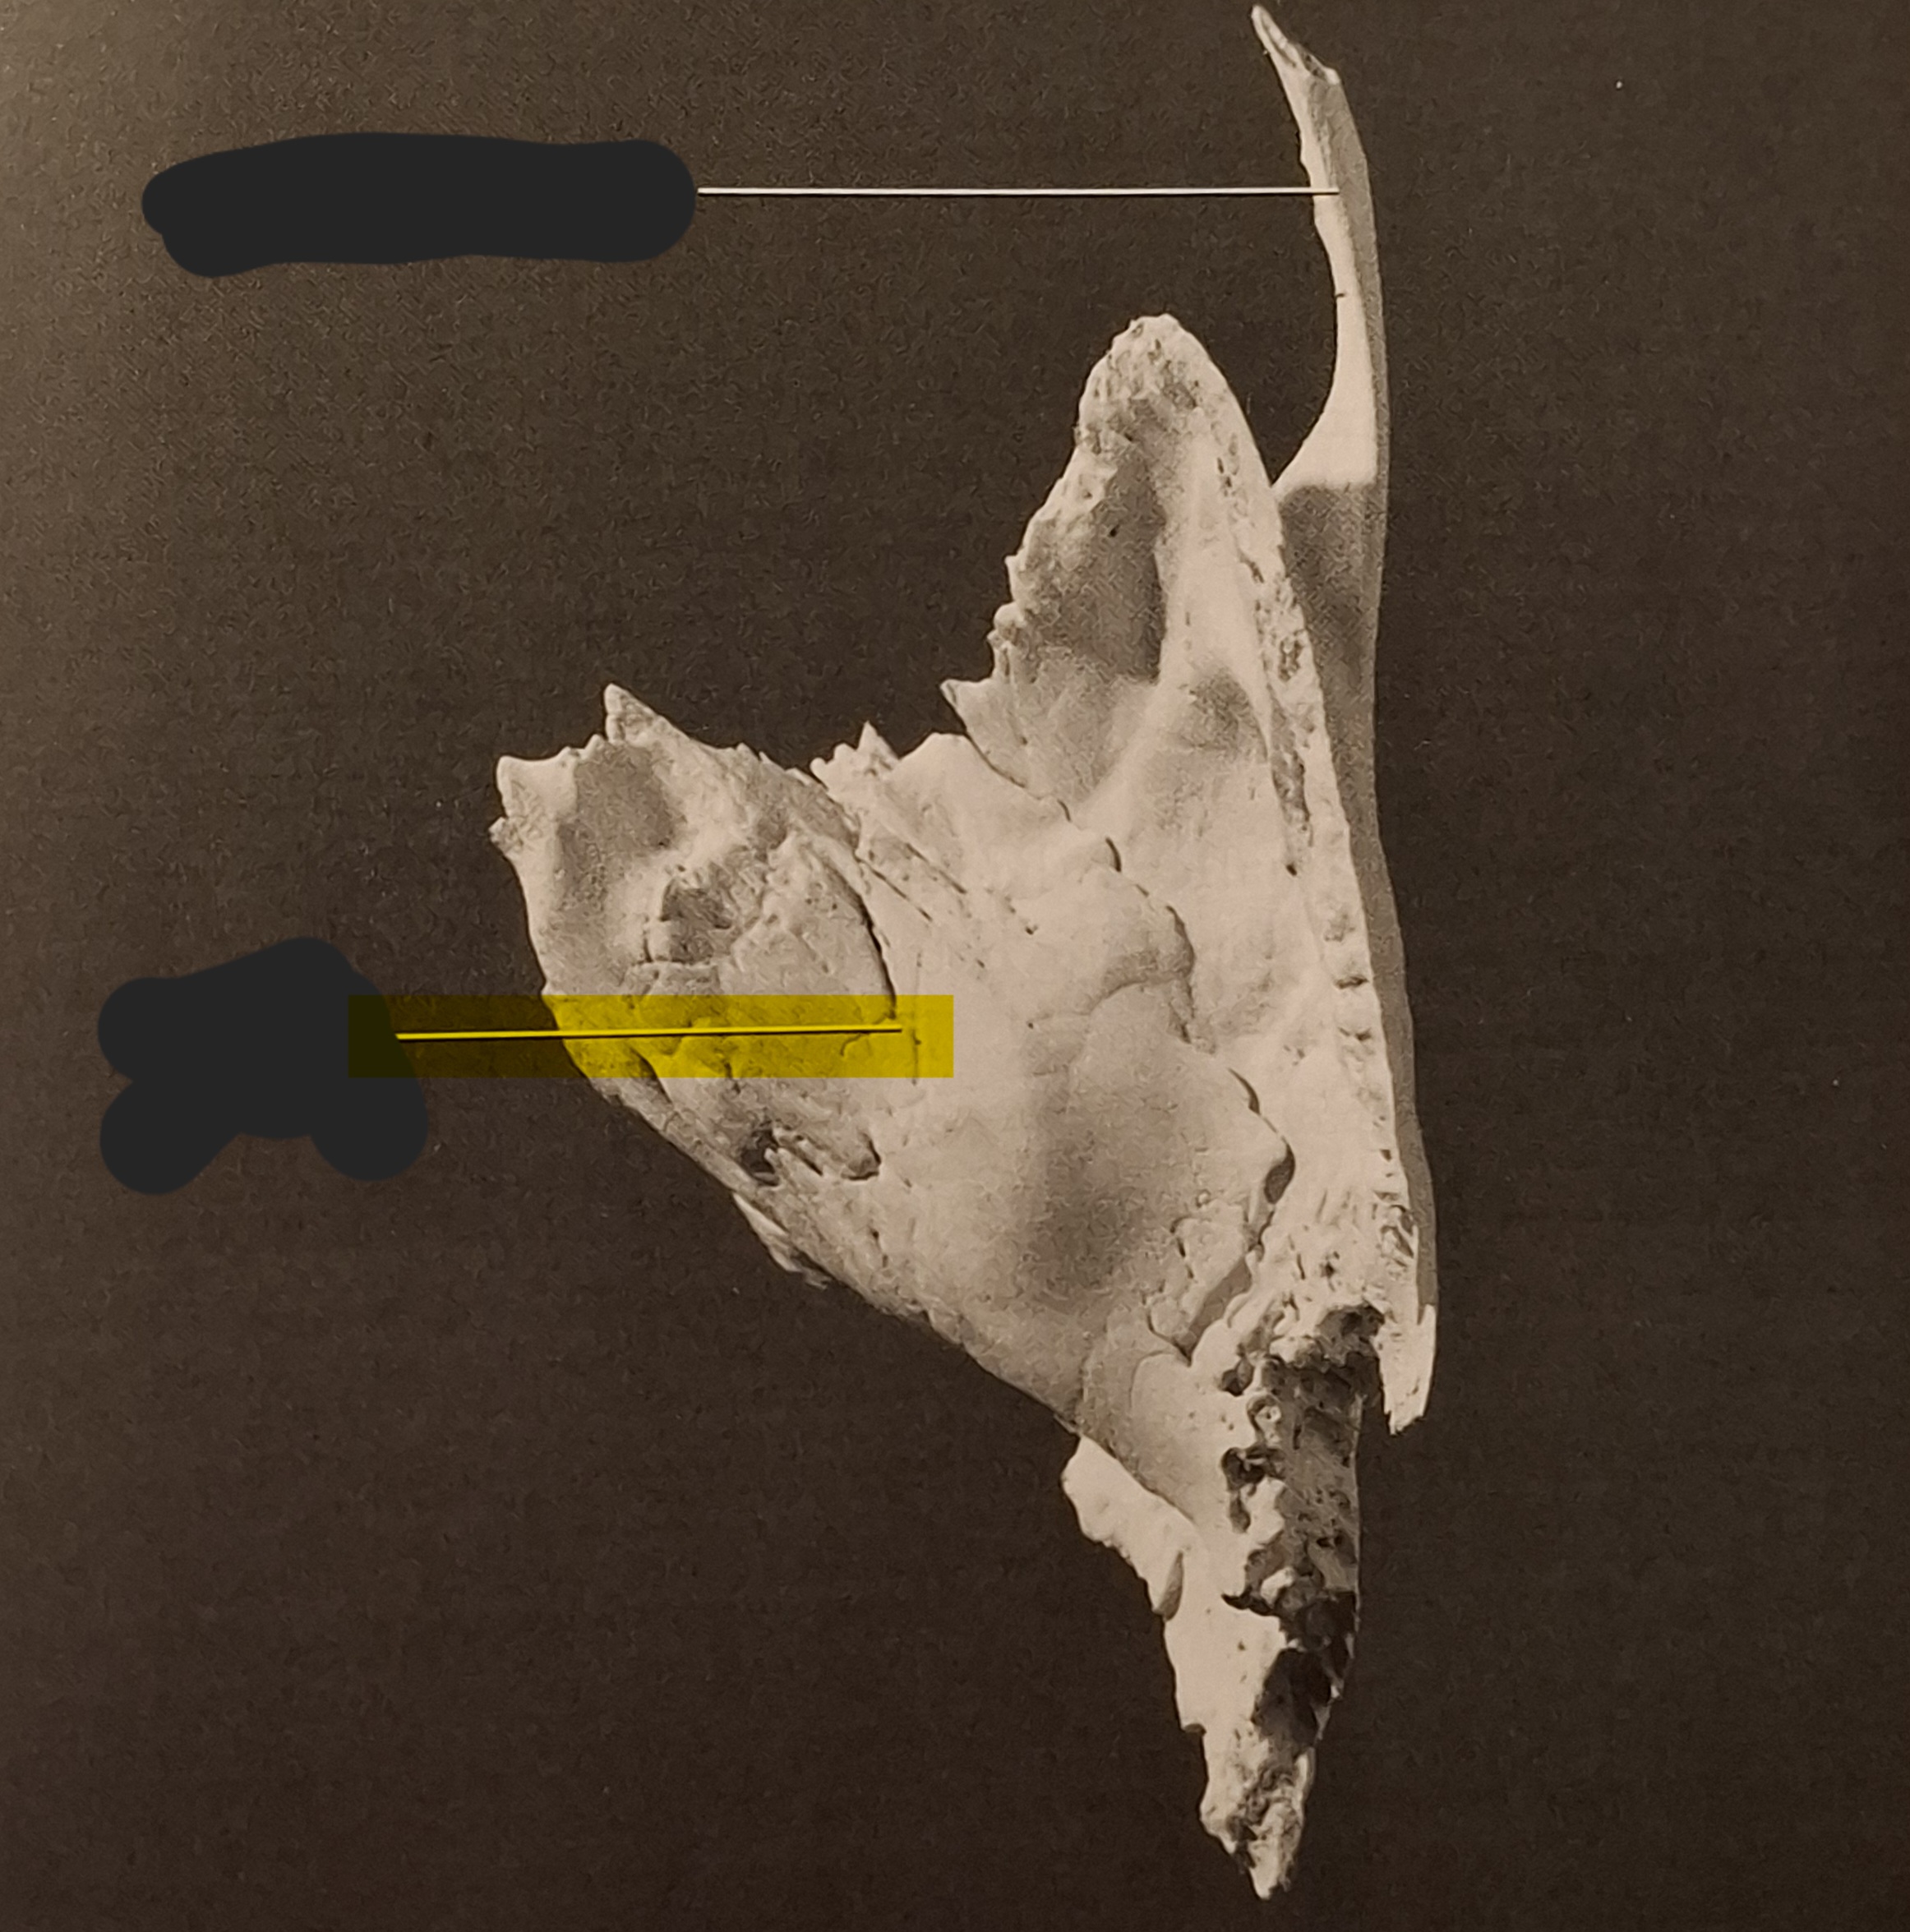

Palatine